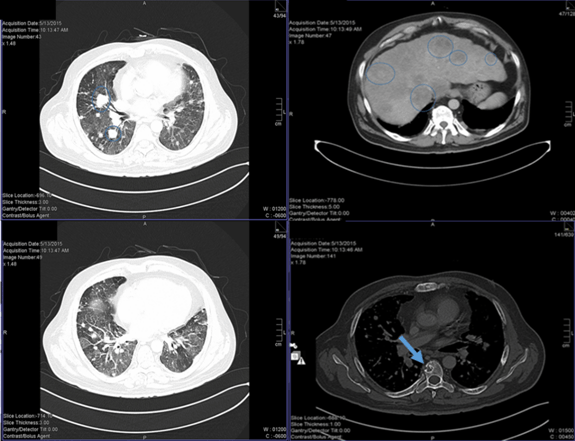

Figure 3: (A, B) CT chest with multiple bilateral pulmonary nodules. (C) CT abdomen showing multiple hypodense lesions in the liver. (D) CT chest showing osteolytic lesions in the vertebral body.